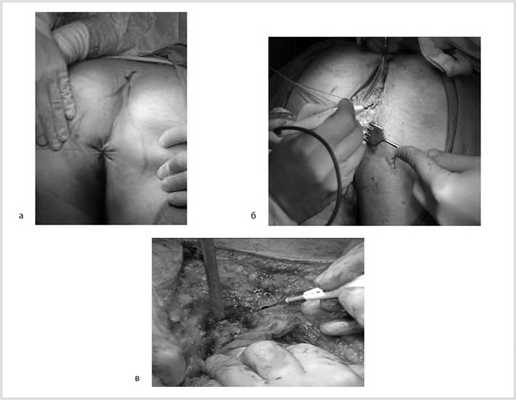

Далее больной перевернут на живот в положении по типу «перочинного ножа» (рис. 7).

Рис. 7. Положение больного на столе (а). Вид операционного поля промежности (б).

После обработки операционного поля мобилизация прямой кишки продолжена из широкого промежностного доступа. Выполнено ушивание заднего прохода кисетным швом, намечены края резекции. В проекции крестцово-копчикового сочленения кожа и подкожная жировая клетчатка рассечены до задней крестцово-копчиковой связки. Последняя пересечена в поперечном направлении. Выполнена ампутация копчика с последовательным пересечением передней крестцово-копчиковой и крестцово-прямокишечной связок (рис. 8).

Рис. 8. Этапы операции. а — ушивание ануса; б — рассечение кожи и подкожной жировой клетчатки; в — пересечение крестцово-копчиковых связок.

Далее прямая кишка с опухолью в едином блоке мобилизована острым путем от предстательной железы и правой стенки таза, после чего выполнена цилиндрическая брюшно-промежностная экстирпация прямой кишки. Малый таз дренирован двумя силиконовыми дренажами и ушит наглухо (рис. 9).

Рис. 9. Этапы операции. а — мобилизация простаты; б — дренирование малого таза; в — конечный вид раны.